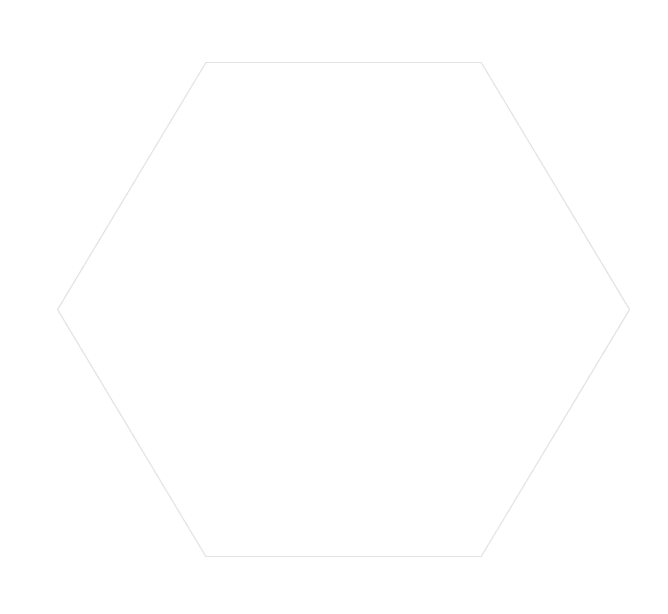

数据的精确采集提取,影响种牙方案的设计,麦芽口腔MAC数字化精确数据采集中心,采用三维锥形束X线取代扇形螺旋CT,一次采集头部完整近30项数据,重组三维立体超高清图像。

深圳第11台德国数字化CBCT2015年落户麦芽口腔

2015年麦芽口腔正式起航引入德国卡瓦数字化CBCT,实现了口腔数据的精确采集,标志着麦芽迈出数字化口腔第一步。